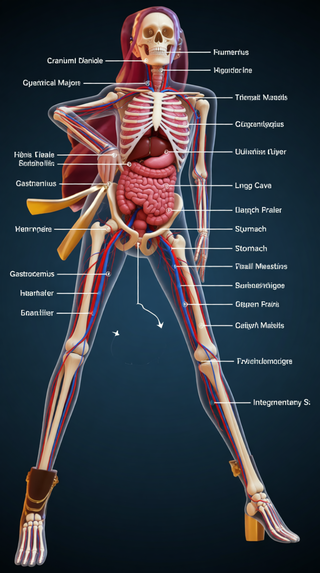

Creates ultra-detailed, multi-layer 3D anatomical visualizations from reference photos.Open

Creates ultra-detailed, multi-layer 3D anatomical visualizations from reference photos.Open

Transform photos into scientific anatomical illustrations.Open

Transform photos into scientific anatomical illustrations.Open